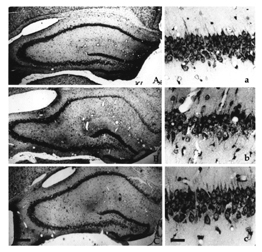

Cerami and his colleagues looked first at an infrequent type of spinal cord injury, one that’s similar to stroke. If blood flow to the spinal cord is blocked–say, during abdominal surgery–paralysis may result. In the Feb. 19 Proceedings of the National Academy of Sciences, the scientists described an experiment in which rabbits received an injection immediately after surgery that blocked blood flow to the spinal cord. Animals given EPO had better muscle control of their hind limbs than did rabbits getting saline instead of the hormone. Over the next 2 days, muscle function worsened in the saline-treated animals, but the EPO-treated rabbits improved. At the end of that time, they also showed less nerve damage than did those that got injections of saline.

In the July 9 Proceedings of the National Academy of Sciences, the researchers demonstrated that EPO counteracts the nerve damage associated with two more common kinds of traumatic spinal cord injury in people. In rats with spines damaged by compression of the nerves, a single dose of EPO after injury boosted the animals’ hind leg movements within 12 hours of the injury compared with those of rats getting placebo injections. After 28 days, the EPO-treated rats–some of which were given additional doses on the second and third days after injury–had near-normal movement of their hind limbs, Cerami says, while animals given the dummy injections were still paralyzed.

The researchers also examined direct trauma to rats’ vertebrae and spinal cord that caused injuries and paralysis more severe than those resulting from compression. The researchers didn’t see any recovery of muscle movement or limb function in this group at first, whether or not the animals were given EPO. However, between the 4th and 12th day after injury, animals treated with one dose of EPO an hour after injury had better muscle tone and more coordinated leg movements and were also better at swimming than rats treated with a placebo were. When the researchers examined the rat spines 28 days later, the rats given EPO showed fewer signs of swelling and cell death surrounding the injury than placebo-treated rats did.